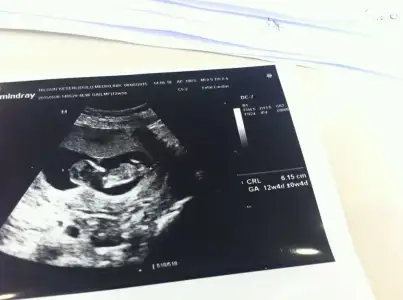

Erkeğe daha çok benzettim ikinci resimden dolayı. Ama kesin diyemem.Kızlar cinsiyet konusunda tahmin alabilirmiyim??Eki Görüntüle 1522208 Eki Görüntüle 1522219

Henüz nubu oluşmamış bu teori için 12-13 haftalar en ideal zamanlar.

Çok teşekkür ederim cevabın için. Ben 3 hafta sonra tekrar geleyim bariHenüz nubu oluşmamış bu teori için 12-13 haftalar en ideal zamanlar.